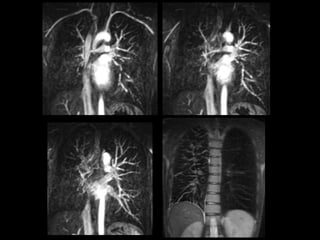

Protocolo AngioTC Torácico

• Desde base cuello hasta nivel de arterias renales

para incluir troncos supraaórticos y arterias

infradiafragmáticas.

• 0.8/1 mm. grosor de corte

• 100-120 ml contraste yodado no iónico a 4cc/sg.

• ROI en Aorta descendente.

• Reconstrucciones multiplanares y volumétricas

(MIP y VR): coronales (arterias mamarias internas

e intercostales) y axiales (arterias frénicas

inferiores y tronco celiaco).

Protocolo AngioTC Torácico •Desde base cuello hasta nivel de arterias renales para incluir troncos supraaórticos y arterias infradiafragmáticas. • 0.8/1 mm. grosor de corte • 100-120 ml contraste yodado no iónico a 4cc/sg. • ROI en Aorta descendente. • Reconstrucciones multiplanares y volumétricas (MIP y VR): coronales (arterias mamarias internas e intercostales) y axiales (arterias frénicas inferiores y tronco celiaco).